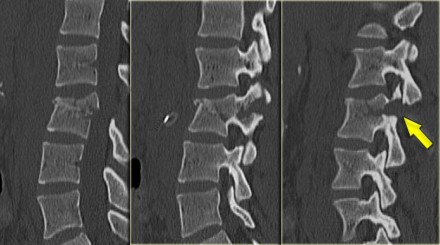

On the left images of a 31 year old male.

He was working on a roof, fell approximately 5 meters landing on his feet.

He complained of pain in left lower extremity and lower back.

First study the images, then continue reading.

On the x-ray there is a hyperflexion injury of L1 with

involvement of the anterior column and possible involvement of the

middle column.

The sagittal reconstructions of the CT demonstrate that the posterior

part of the vertebral body is of normal height, but there is some

involvement of the posterior part of the vertebral body.

There is debate on how to treat these patients and if there is any role of MRI in these cases.

If you are aggressive you could call this a two column injury, which would require stabilizing surgery.

If you are conservative you could call this an injury with only minor involvement of the middle column.